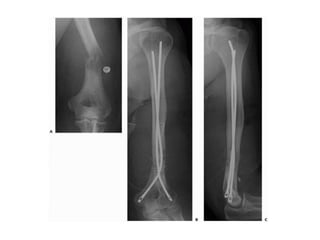

• Upper Extremity

• Scapula, clavicle – non operative

• Proximal humerus – prosthesis (long stem),

intramedullary nail with multiple screws

• Humerus Diaphysis – locked IM nail > plating

• Distal humerus – prosthesis, retrograde flexible IM nails

> bicondylar plating

• Forearm – Rare. IM nails or plating